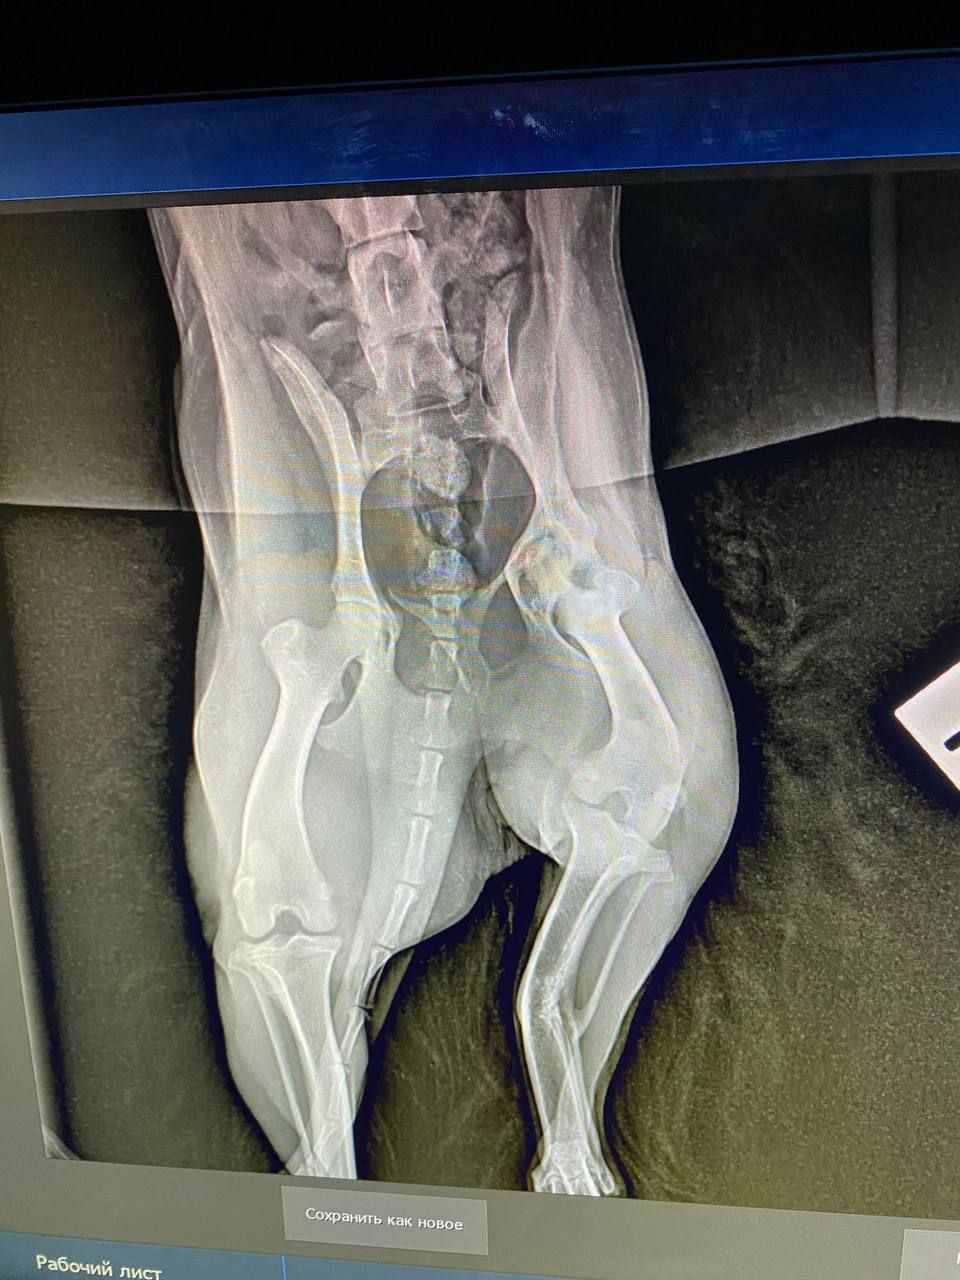

Сходили к ортопеду, у Люси перелом лапы в трех местах, уже сросшийся. Предлагают операцию в 2 этапа.

Завтра с Люсей едем на повторную консультацию в Колпино. У нее пока течка, отложили немного с ногой вопросы, не горит уже, срослось все вкривь и вкось(

вот это перелом...она не под машину или какой транспорт попала, интересно. У нее получается в нижнем переломе верхняя часть кости срочлась с серединой нижнего обломка?

Похоже, что под машину. Когда ее нашли, видимо, свежий был перелом. Но пока волонтеры там мумили, хотя мы сразу согласились забрать, срослось все наперекосяк(Анастасия Нибелунг писал(а): ↑10 апр 2026, 20:33 вот это перелом...она не под машину или какой транспорт попала, интересно. У нее получается в нижнем переломе верхняя часть кости срочлась с серединой нижнего обломка?

Возможно будет 3 этапа операций, поскольку у Люсьенки по КТ стало понятно , что еще повреждена голень, вывернута неестественно вправо.